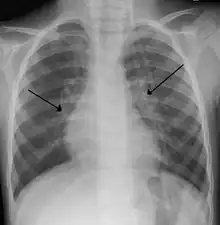

An X-ray of a child with RSV showing the typical bilateral perihilar fullness of bronchiolitis.

The diagnosis is typically made by clinical examination. Chest X-ray is sometimes useful to exclude bacterial pneumonia, but not indicated in routine cases.[17] Chest x-ray may also be useful in people with impending respiratory failure.[18] Additional testing such as blood cultures, complete blood count, and electrolyte analyses are not recommended for routine use although may be useful in children with multiple comorbidities or signs of sepsis or pneumonia.[7][18]